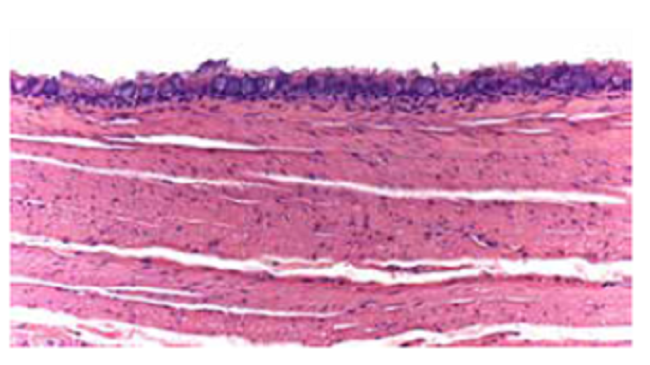

En el estudio anatomopatológico de la masa se encontró un epitelio columnar ciliado, áreas de la pared que correspondían a cartílago, músculo liso, glándulas bronquiales y tejido nervioso (figuras2 y 3). Se trataba de un quiste que contenía un líquido claro acelular.